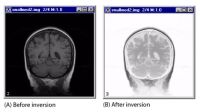

Creating negatives of images with Invert LUT

An image before and after inversion

To create a negative image

1. Select the image window of the image you want to invert.

2. Click Invert LUT.

Based on the 256-step color values scale, MIPAV assigns the inverse value to each pixel of the image (refer to Figure 27).

Tips: You may wish to apply a LUT to the image or adjust the histogram of the image first before applying creating the negative.The Invert LUT icon is a toggle. To change the image back to its previous appearance, simply select Invert LUT again. To change the image back to its original appearance, select Reset LUT.

Note: Invert LUT appears on two different windows: in the Image toolbar in the MIPAV window (select Toolbars > Image toolbar to display the toolbar) and in the LUT toolbar in the Lookup Table window.